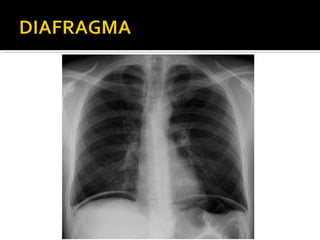

Este documento fornece parâmetros técnicos para realizar uma radiografia de tórax, incluindo posicionamento correto do paciente, dose adequada de radiação e estruturas anatômicas a serem avaliadas, como coração, pulmões, pleura, diafragma e ossos do tórax.